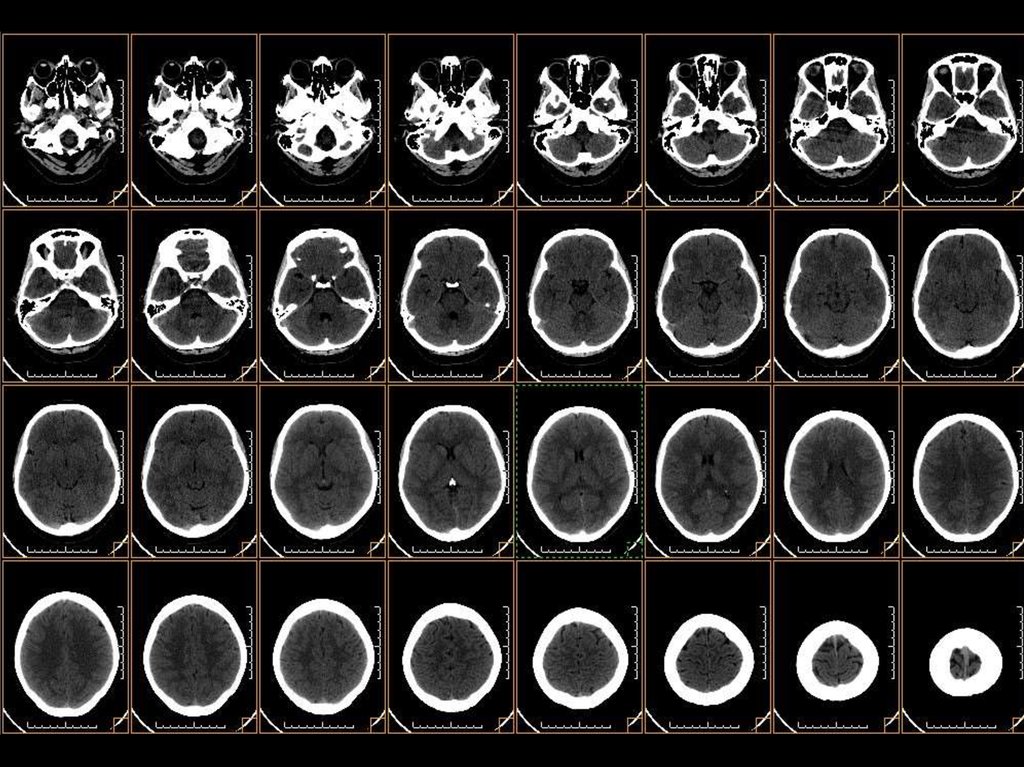

1.

исследование головного мозга